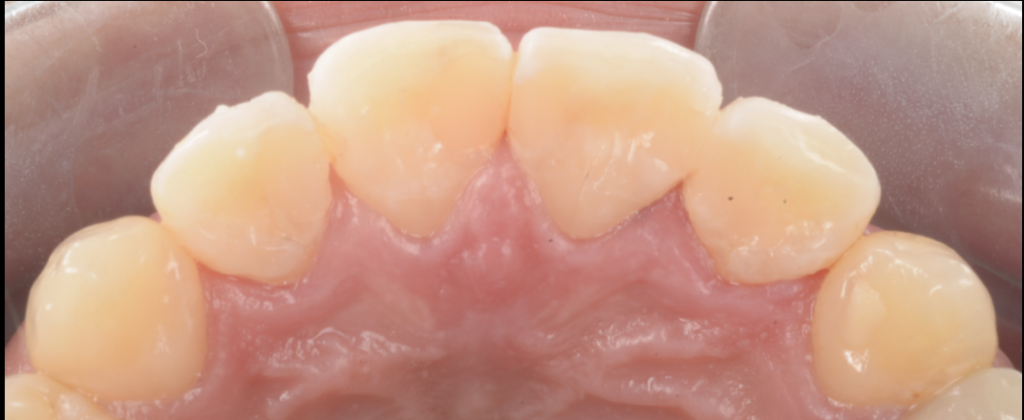

【今回の症例から】「詰めてあるのに、実は中で虫歯が進んでいた」

今回お伝えしたいのは、ここです。

患者さんは「詰め物が入っているから大丈夫」と思っていた。

見た目にも大きな痛みはない。

ただ、よく見ると着色が目立つ、そして詰め物が浮いているように見える。

そこで再治療のために詰め物を外してみると――

- 修復物の下で、虫歯が広がっていた

- 歯質が想像以上に脆く、削ると崩れる

- 結果として、当初の予想よりも歯の大半を失う形になってしまった

このケースは決して珍しくありません。

接着が破綻したところから微小漏洩が起き、そこに細菌が入り、見えない場所で増殖してしまう。

そして気づいた時には、表面の変色よりもずっと深部で病変が進行している――。

“詰めた=治った”ではなく、

詰めた後にこそ、再発させない条件(密閉・咬合・管理)が必要だということを、症例は教えてくれます。